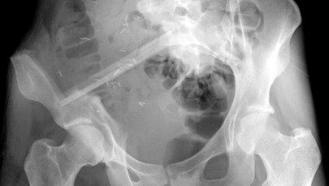

vermelden. Ich erinnert euch alle an die Bilder, die wir euch nach der Operation gezeigt haben. Hier ist es auf dem Foto noch einmal zu

sehen. Es ist ihr operativ das rechte Wadenbein aus dem Bein entfernt und als Stütze in das Becken eingesetzt worden, dort, wo vorher

die Beckenschaufel war. Das ist schon ein Meisterwerk ärztlicher Kunst gewesen. Und Gott hat Gelingen und Segen dazu gegeben. Die

Schmerzen, die Puschel in den letzten Tagen mehr hatte als sonst, rühren jetzt daher, dass der Knochen etwa an der Stelle, auf die der

Pfeil zeigt, richtiggehend durchgebrochen ist. Die Ärzte sprechen von einem Ermüdungsbruch. Der Knochen ist in der Substanz während

der Zeit der Chemo und der dadurch beabsichtigten Verhinderung der Neubildung von Zellen (Zielpunkt waren natürlich die

Krebszellen) zurückgegangen und ermüdet. Das große Problem ist, dass nun noch weniger Stabilität da ist und der Knochen erst wieder

zusammenwachsen muss. Darum werdet ihr, wenn ihr hier reinschaut, nun wieder mehr Bilder von “Puschel im Liegen” sehen. Das ist